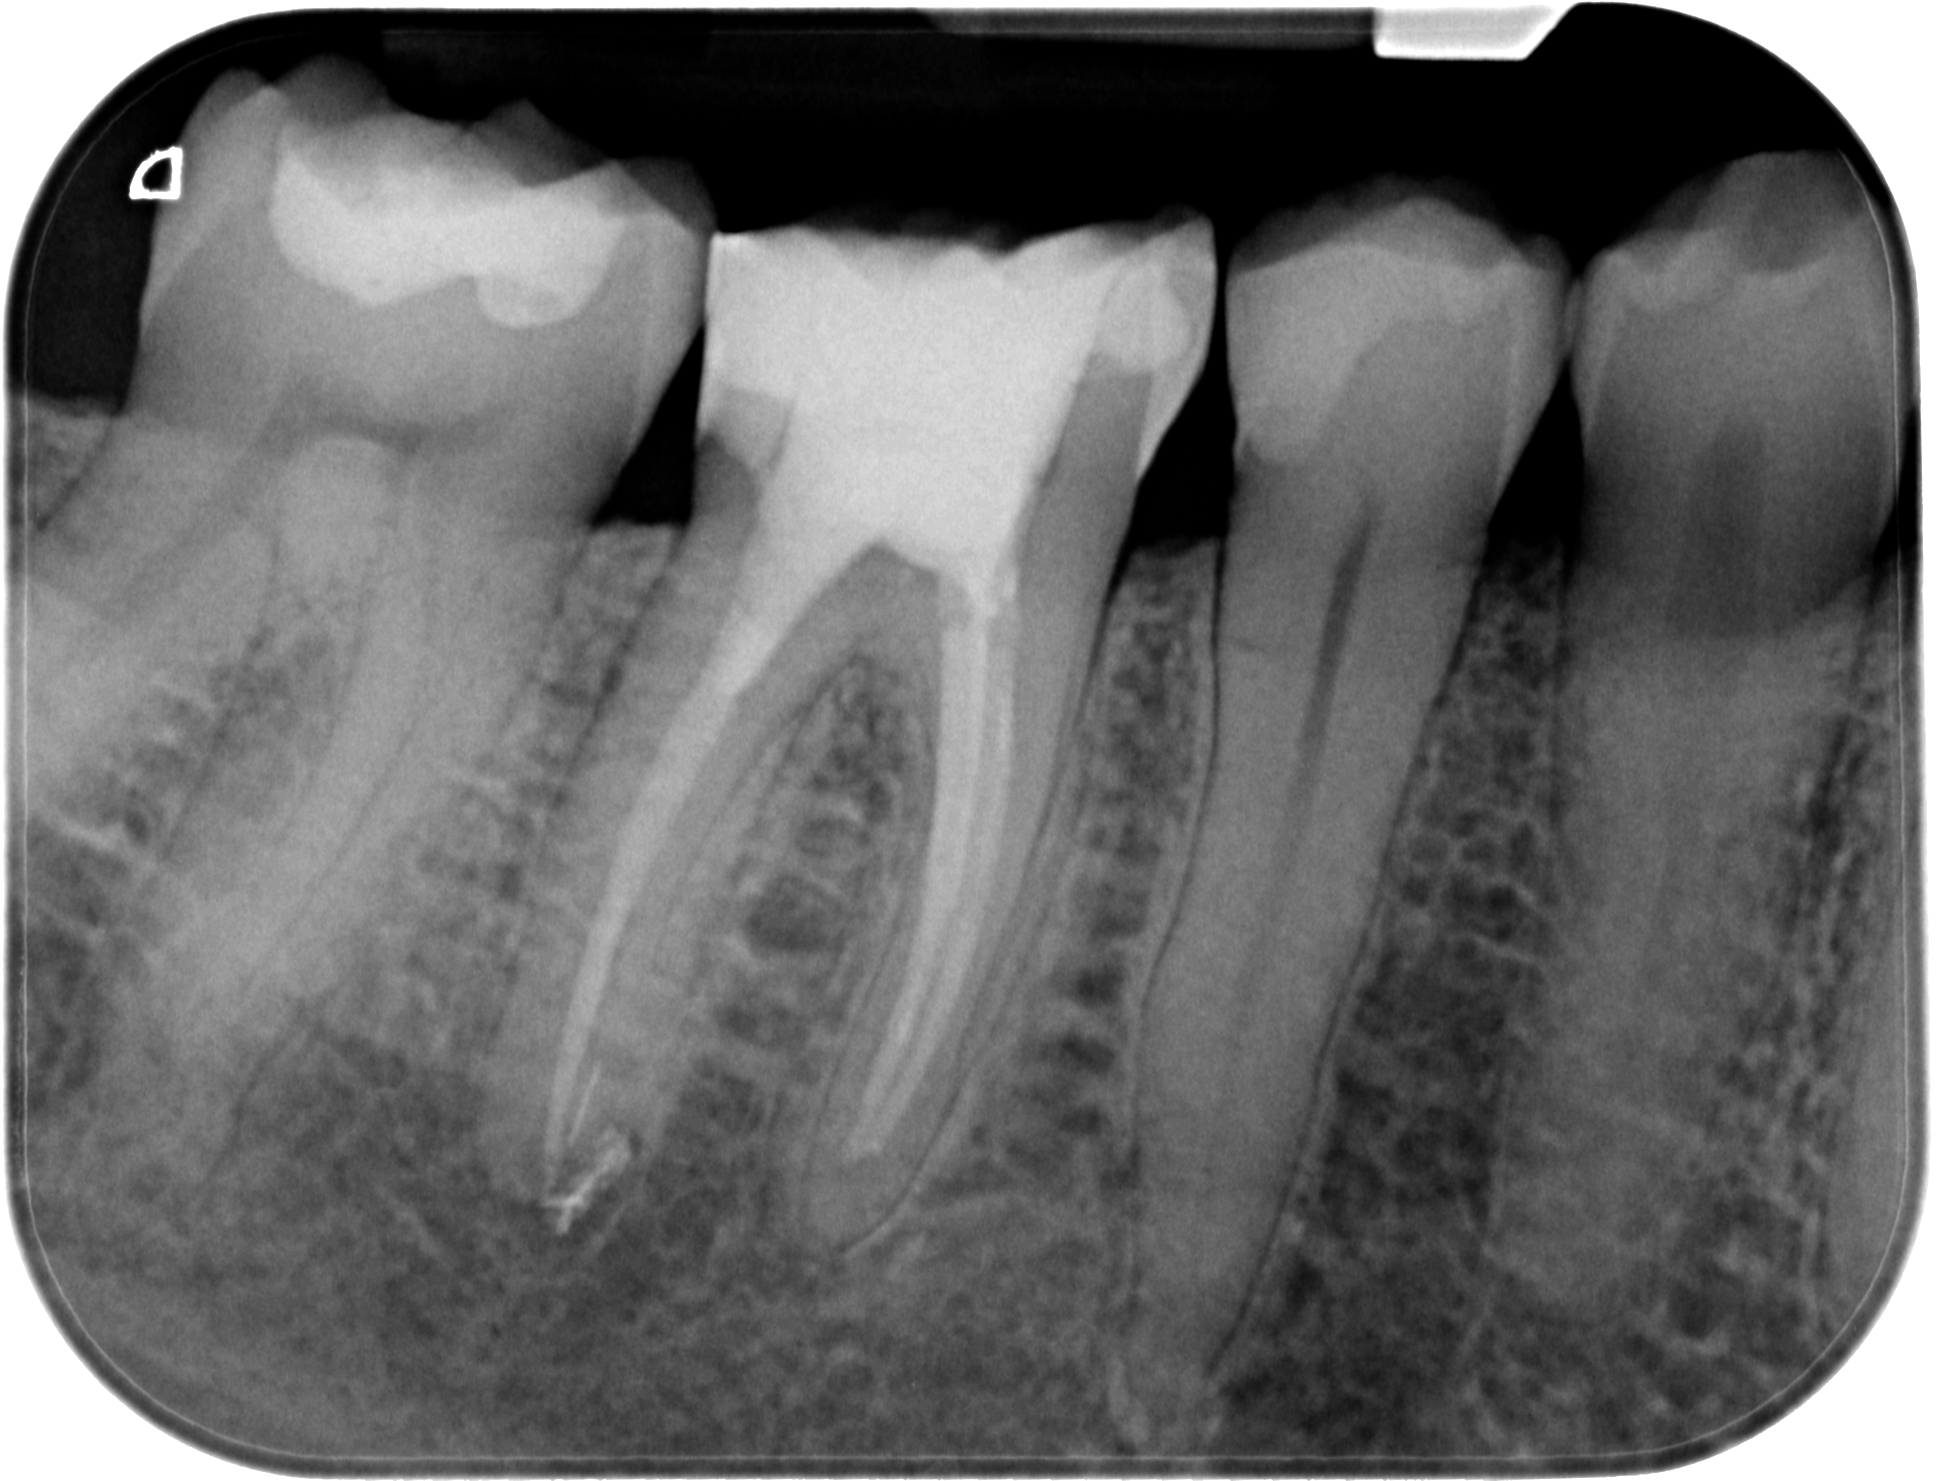

15.08.2019 Patientin DW, geb. am 12.04.1968, Zahn 46, WF Revision